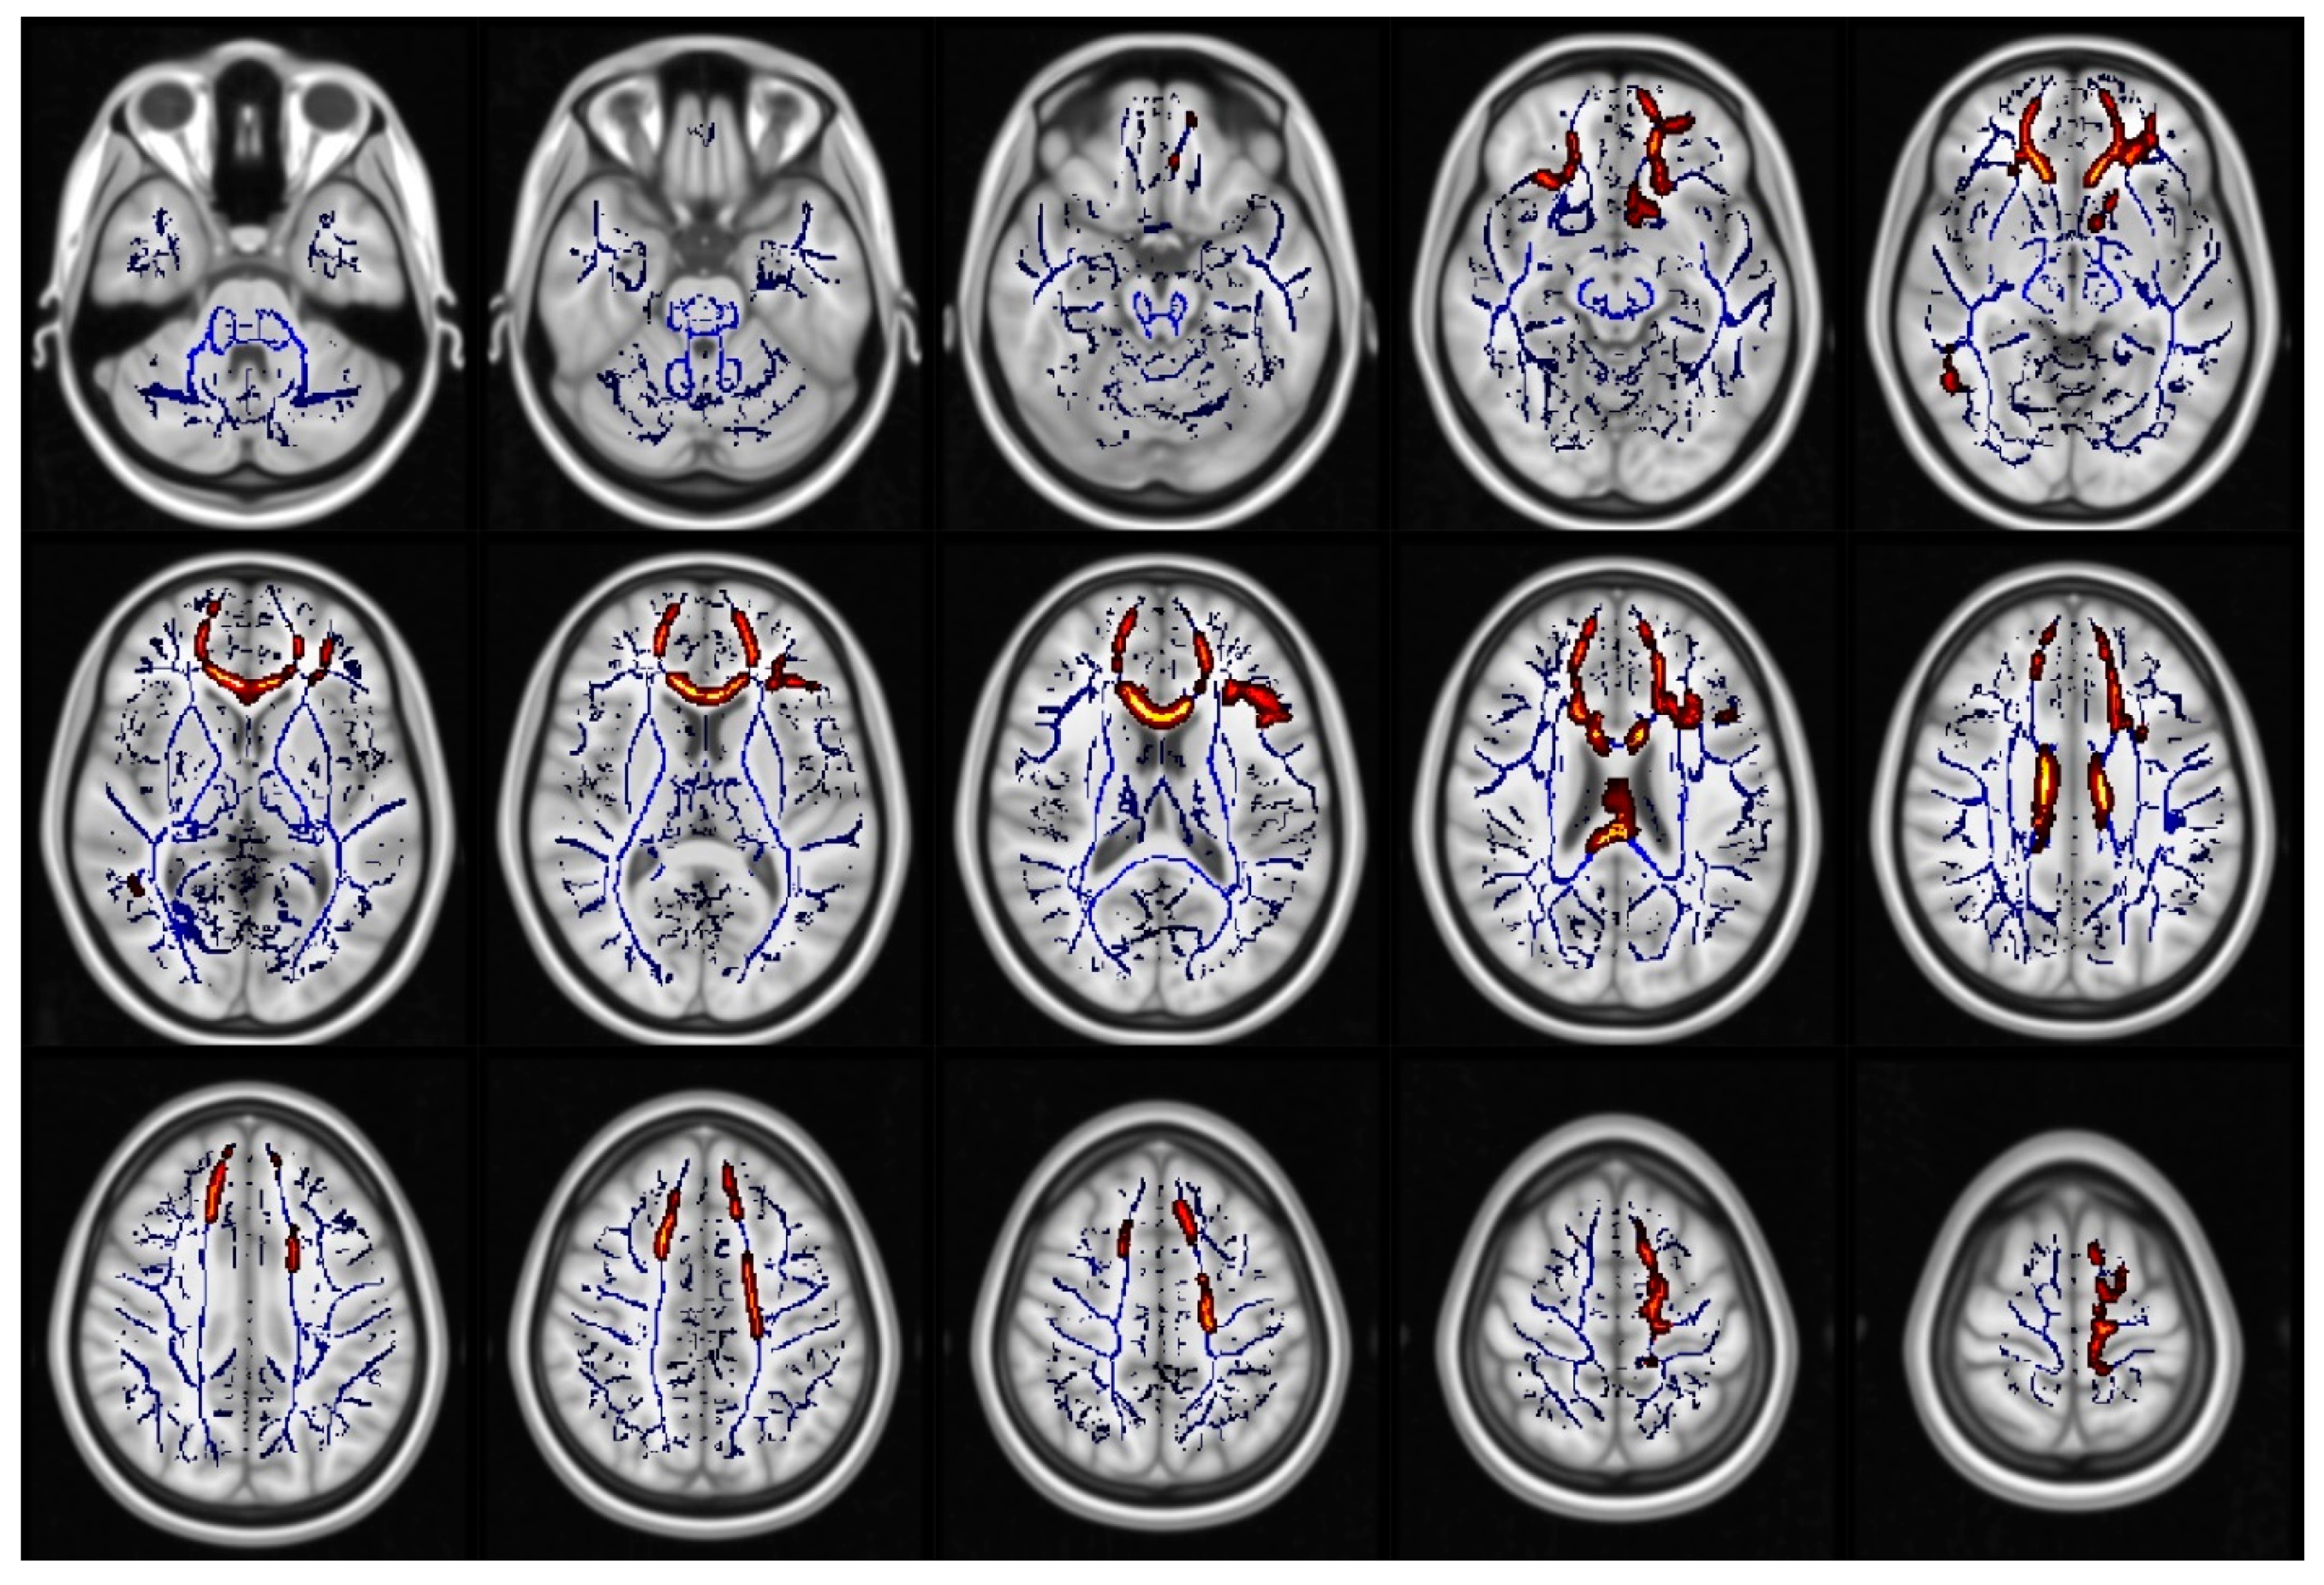

- Smith, S.M.; Jenkinson, M.; Johansen-Berg, H.; Rueckert, D.; Nichols, T.E.; Mackay, C.; E Watkins, K.; Ciccarelli, O.; Cader, M.Z.; Matthews, P.M.; et al. Tract-based spatial statistics: Voxelwise analysis of multi-subject diffusion data. NeuroImage 2006, 31, 1487–1505. [Google Scholar] [CrossRef] [PubMed]

- Smith, S.M.; Nichols, T.E. Threshold-free cluster enhancement: Addressing problems of smoothing, threshold dependence and localisation in cluster inference. NeuroImage 2009, 44, 83–98. [Google Scholar] [CrossRef] [PubMed]